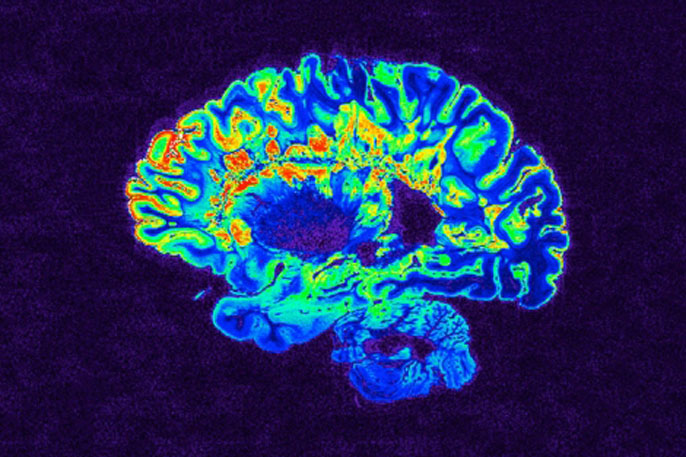

Although the research team could not directly observe evidence of rebuilding of myelin in trial participants using magnetic resonance imaging (MRI), Chan and Green said that this reflects a weakness of current MRI techniques as a tool for this purpose rather than evidence that myelin regeneration did not take place. “We still don’t have imaging methods that have been proven to be able to detect remyelination in humans,” said Chan.